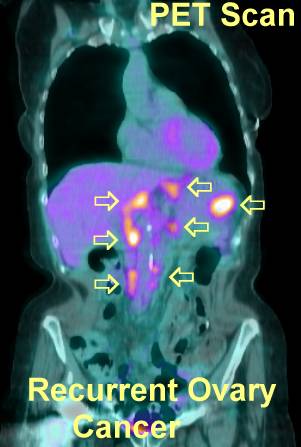

Ovarian Cancer: Decoding Radiology Reports

CT or CAT Scan Computed tomography When ovarian cancer is suspected, usually surgery is the next step. Ovarian Cancer; Testing & Diagnosis; Ovarian Cancer: Decoding Radiology Reports About Health Follow us: We deliver. Get the best of About Health in your inbox. ... Read Article